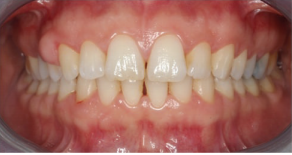

患者38岁,女,发现牙龈无痛性增生肿胀。患者未服用任何药物,未处于妊娠期,家族史无异常。

口内检查发现患者13、14牙间牙龈肿胀,质硬,无蒂,牙龈周围轻度菌斑堆积,牙龈轻度红肿。13、14牙不松动。